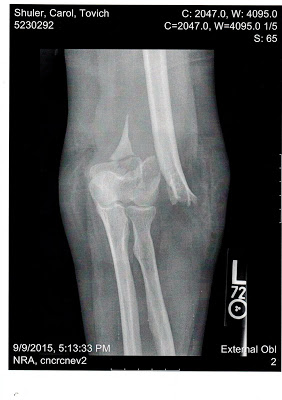

![]() |

| X-ray of Carol Shuler's arm, broken by a sheriff's deputy |

Marissa Morris apparently took a punch to the face without being hurt too badly. This must be one tough woman -- or perhaps Bonar hit her more with his palm than with his fist. The punch had to have hurt, and Morris was fortunate to escape without a broken nose or other structural damage. As for our situation in Missouri, X-rays show that Carol's left arm was essentially snapped like a twig, with the break so extreme that it required trauma surgery -- and she likely will never regain more than 75 percent use of her arm.